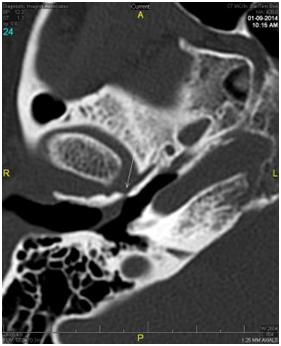

Two months later, a third operative procedure was performed for excision of a further recurrence of the granuloma in the anterior superior portion of the ear canal. Following this third procedure, the idea of a herniation through a bony defect in the anterior canal wall was finally considered. A second CAT scan of the temporal bones was performed. This scan revealed a soft tissue density closely associated with the tympanic membrane in the external auditory canal on the right just anterior to it and what appeared to be a small defect or thinning of the anterior canal wall just posterior to the temporomandibular joint. Axial and coronal views of the defect in the anterior wall are shown in Figures 2 (A & B) and demonstrate conclusively the presence of a patent foramen of Huschke. Further examination revealed motion of the lesion with mastication. The patient’s facial asymmetry was determined to be a consequence of mandibular asymmetry.

Figure 2(B) Reconstructed para-coronal images through the anterior wall of the external auditory canal just posterior to the condylar head of the mandible at the level of the Tmj Joint. Arrow depicts a patent foramen of Huschke.